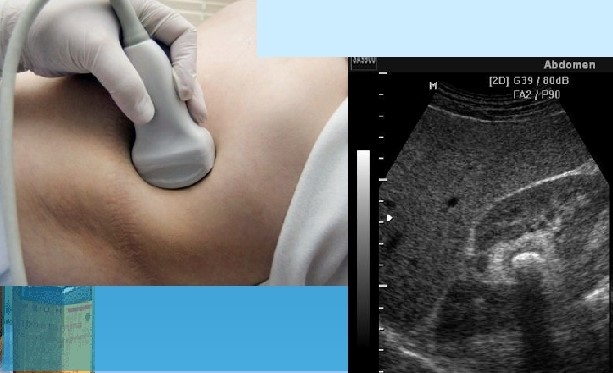

Диагноз МКБ основывают на анамнестических данных (почечная колика), расстройствах мочеиспускания, характерных болях, изменениях мочи (пиурия, гематурия), отхождении с мочой камней, данных ультразвуковых, рентгенологических и инструментальных исследований:

УЗИ. С помощью эхографии выявляются любые рентгенопозитивные и рентгенонегативные камни, вне зависимости от их размера и местоположения.

· УЗИ почек позволяет оценить влияние мочекаменной болезни на состояние чашечно-лоханочной системы. Выявить камни в нижележащих отделах мочевыводящей системы позволяет

· УЗИ мочевого пузыря

· Применяется УЗИ после проведения дистанционной литотрипсии для динамического наблюдения за ходом литолитической терапии мочекаменной болезни с рентгенонегативными камнями